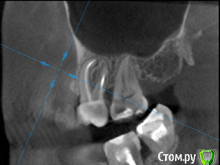

St. Опубликовано 26 августа, 2016 Поделиться Опубликовано 26 августа, 2016 Все три пролечены не очень хорошо, в идеале перелечить и сделать на них коронки. Но на сладкое ни один из них не может реагировать. Возможно реагирует 7 или 3, у которых оголена часть корней за счет вашего парадонтита. 1 Ссылка на комментарий

Гарриевич Опубликовано 27 августа, 2016 Поделиться Опубликовано 27 августа, 2016 возможно пропущенный канал, а возможно Вам "кажется" и реагируют все таки живые зубы. В любом случае данный снимок показывает не очень качественное лечение, но это только снимок 1 Ссылка на комментарий

татьяна tat Опубликовано 27 августа, 2016 Автор Поделиться Опубликовано 27 августа, 2016 возможно пропущенный канал, а возможно Вам "кажется" и реагируют все таки живые зубы. В любом случае данный снимок показывает не очень качественное лечение, но это только снимок Ссылка на комментарий

Beznika Опубликовано 8 сентября, 2016 Поделиться Опубликовано 8 сентября, 2016 на 5 ке материал вывели за апекс. резекцию возможно придётся делать верхушки корня... + карман у вас есть за 6кой. а так всё равно перелечивать надо... масса пористая в каналах и не гомогенная. (не однородная) Ссылка на комментарий

татьяна tat Опубликовано 8 сентября, 2016 Автор Поделиться Опубликовано 8 сентября, 2016 (изменено) на 5 ке материал вывели за апекс. резекцию возможно придётся делать верхушки корня... + карман у вас есть за 6кой. а так всё равно перелечивать надо... масса пористая в каналах и не гомогенная. (не однородная) в каком случае мне грозит резекция? и что с карманом делать?может на срезах так видно...но врач оч. хорошей клиники,на очном приеме,смотря на компьютере кт,сказала,что каналы пролечены на 5+.....не считая того,что немного выведено материала Изменено 8 сентября, 2016 пользователем татьяна tat Ссылка на комментарий